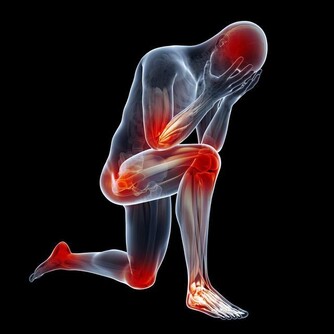

2、 四肢腫脹疼痛

四肢肢是人體供血的最末端,當血管堵塞後,四肢的供血和回血不足就會出現腫脹現象。四肢組織處於缺血缺氧狀態下就會伴隨有疼痛的表現,特別是靜脈血栓發生後,腫脹症狀更為明顯。